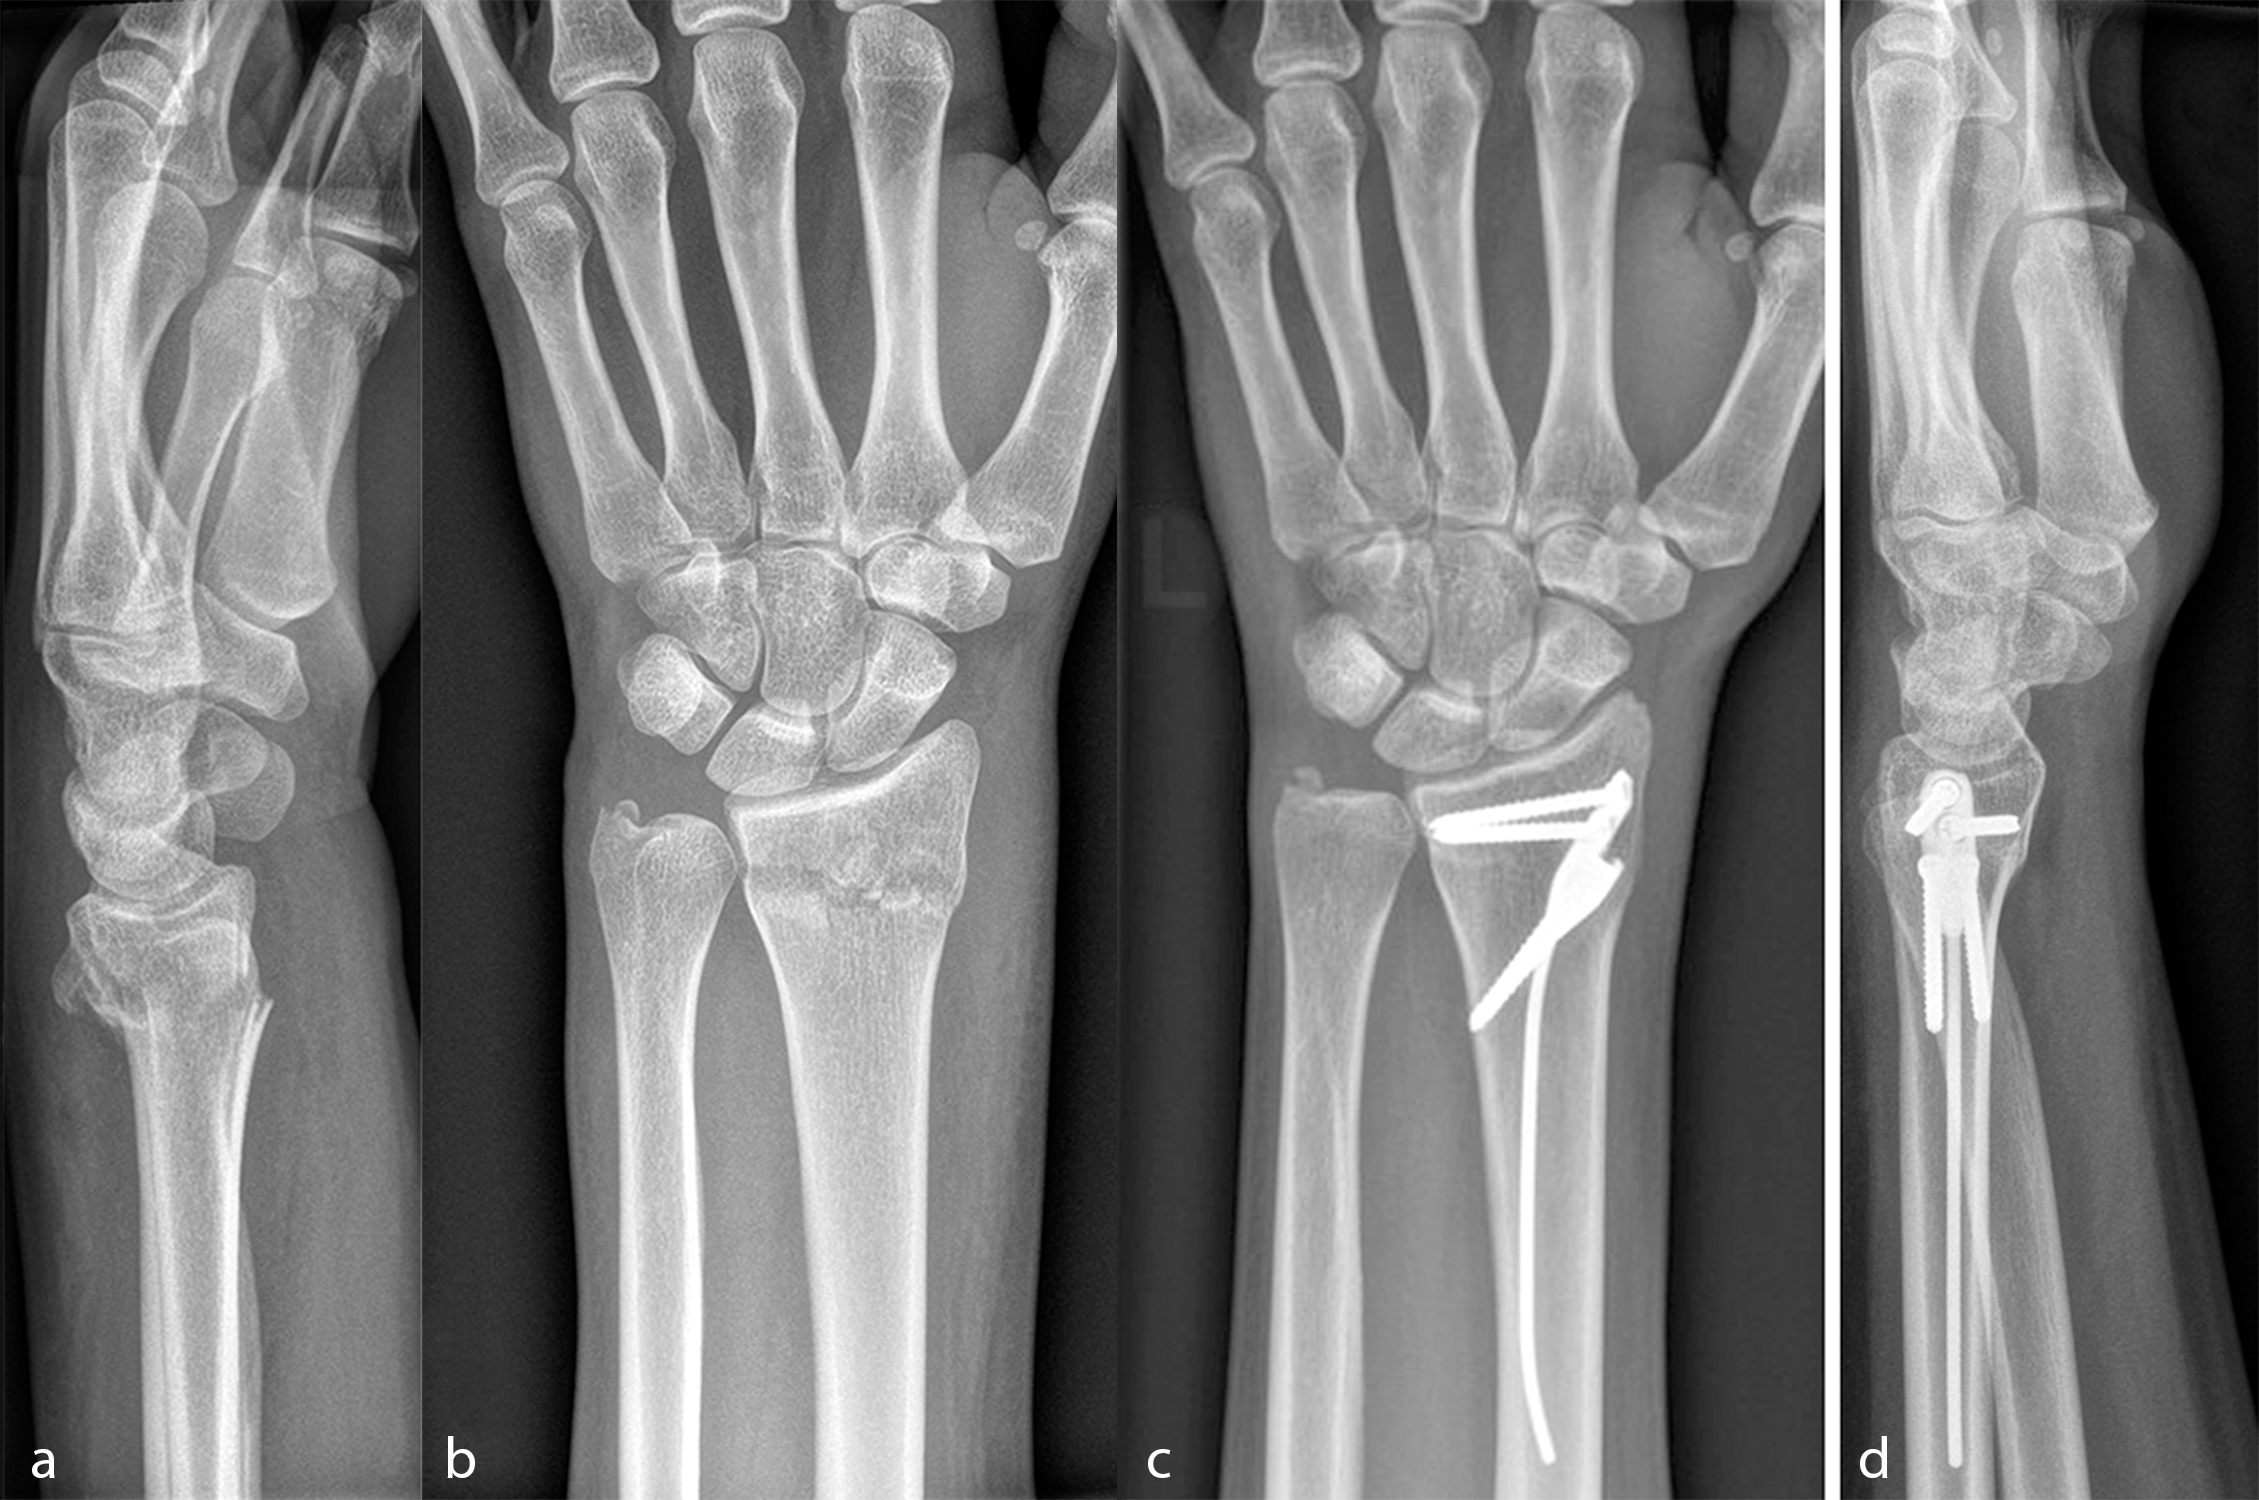

Fig 2: Exemplar case using the DRIM-Nail: (a) Lateral pre-operative radiograph after closed reduction showing a dorsal dislocation of 25° compared to the physiological palmar tilt and a dorsal comminution; (b) AP pre-operative radiograph following closed reduction; (c) AP and (d) lateral radiographs after 3 months with the distal radius fracture healed in anatomical position. (Case kindly provided by Ladislav Nagy, MD, Balgrist Universtity Hospital, Zurich, Switzerland).